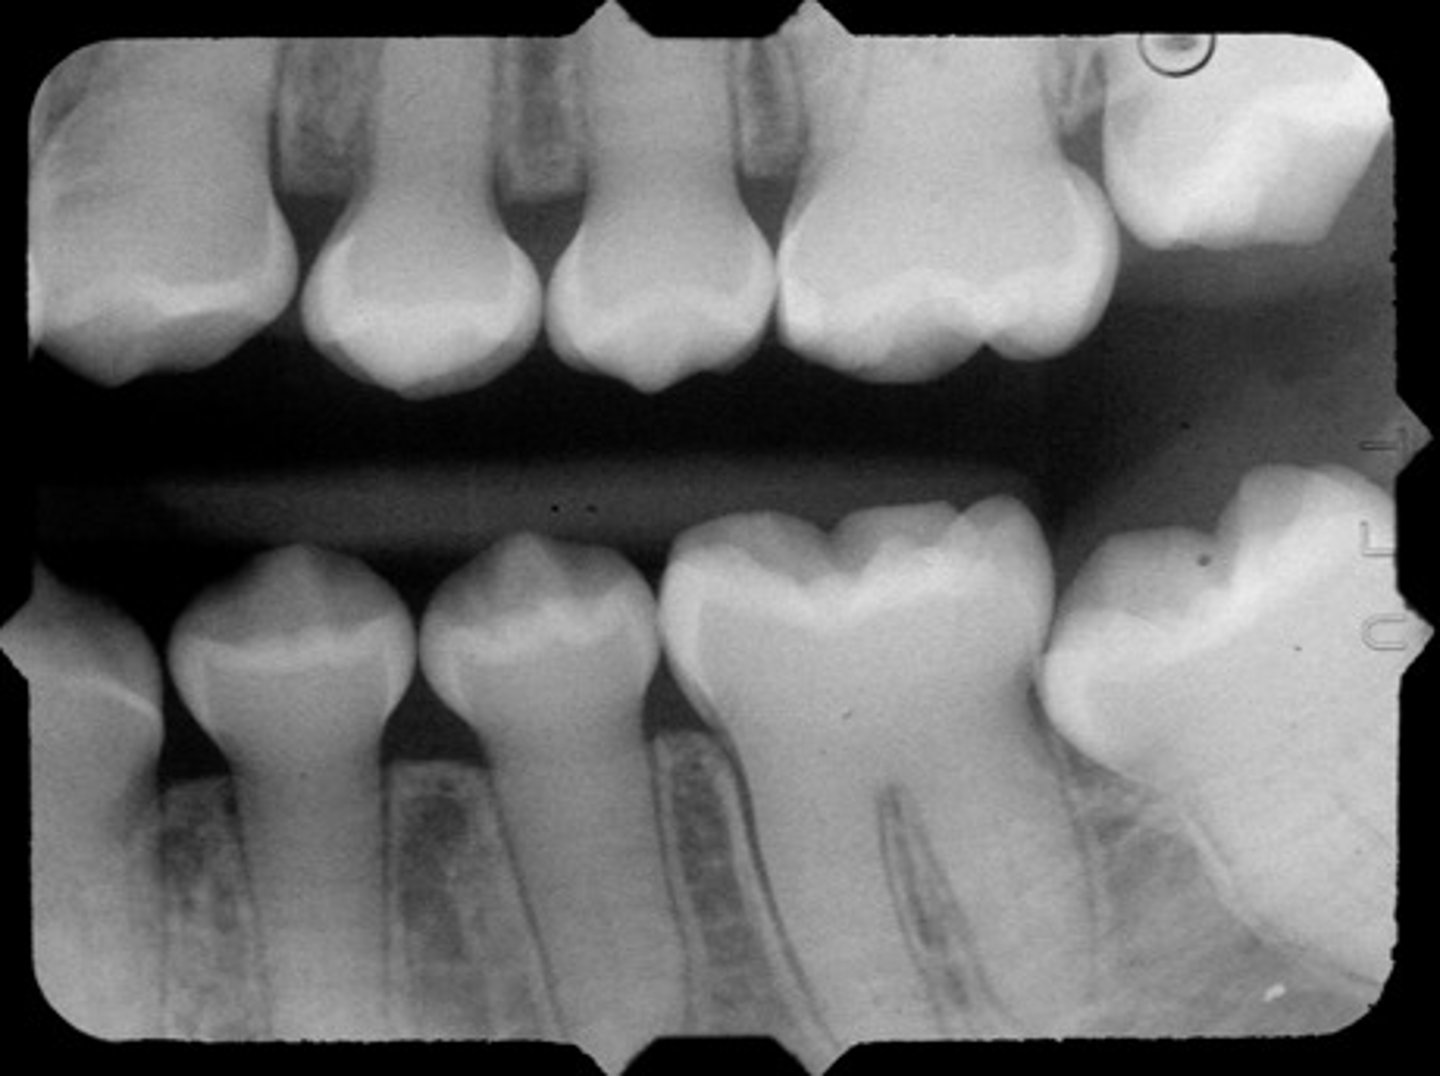

Space between mandibular premolar and molar in an older patient, #31 and #32 are not present, barely in occlusion w/#3. Why is this happening?

- supraeruption

- mesially drifting premolars

- malignant growth

(on 2024 exam)

likely caused by mesially drifiting premolars

- this one is hard to visualize... but knowing this is an older patient makes you think mesial drift. Also, the occlusion w/#3 is preventing #30 from moving mesially (it is tipped)